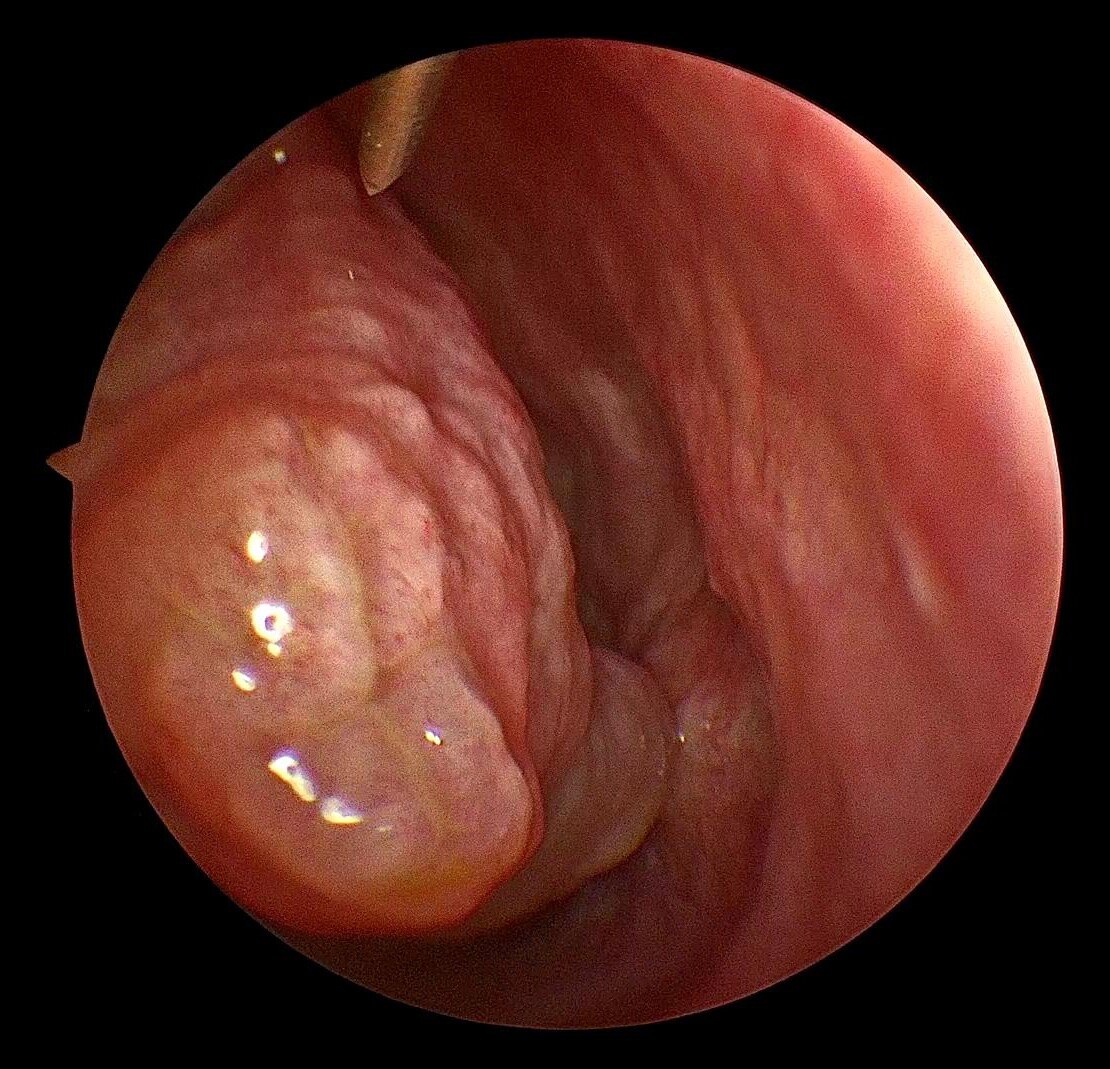

现在随着工业发展及大气污染,过敏性鼻炎患者患病率也明显增高,过敏性鼻炎常表现为鼻甲肿大,苍白水肿,患者鼻塞较明显,鼻音很重,夜间打呼憋气;肥厚性鼻炎也是重要原因之一;再有就是良性的比如鼻息肉、鼻腔乳头状瘤、骨化性纤维瘤等鼻腔堵塞;还有就是鼻腔恶性肿瘤等堵塞整个鼻腔导致的张口呼吸。

鼻甲肥大息肉样变